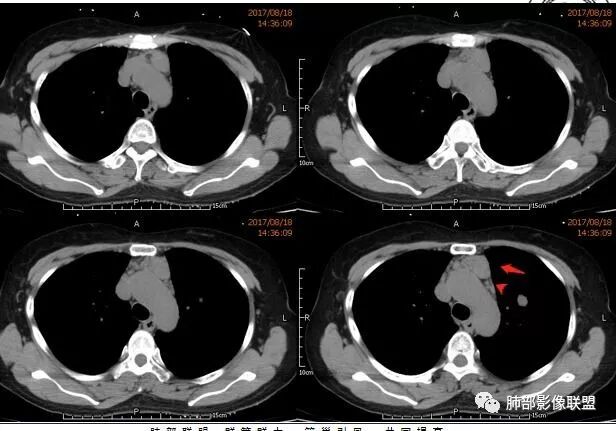

中年女性,因“角膜炎”入院,自用眼液2年,(眼干?)肺部:双肺多发类圆形薄壁气囊+实性结节+GGO,下肺分布为主,纵隔淋巴结肿大,考虑淋巴系统增殖,LIP可能性大,可能继发于干燥综合症;左肺下叶的混合磨玻璃结节形迹可疑,边界清晰,内部疑似空泡,扩张扭曲支气管,极像肺癌,伴双肺转移?待排吧

wonderful

多发气囊,气囊内可见血管进入,因患者眼干伴类风湿,可能有干燥综合征,那LIP可能性大。因为不是育龄期发病,可排除LAM。患者左纵膈淋巴结肿大,且有融合趋势,结合左下肺病灶,考虑合并恶性肿瘤,淋巴瘤?鉴别结节病

左肺下叶混杂密度病灶,其内可见空泡,周围ggo清楚,考虑浸润性腺癌。双肺散在多发薄壁囊腔和实性结节,以胸膜下及血管旁分布位于,气囊可见血管贴边征,双肺小叶间隔及中央间质增厚,局部可见磨玻璃影及树芽征,纵隔内淋巴结肿大,考虑LIP

综上,考虑左下肺浸润性腺癌+LIP